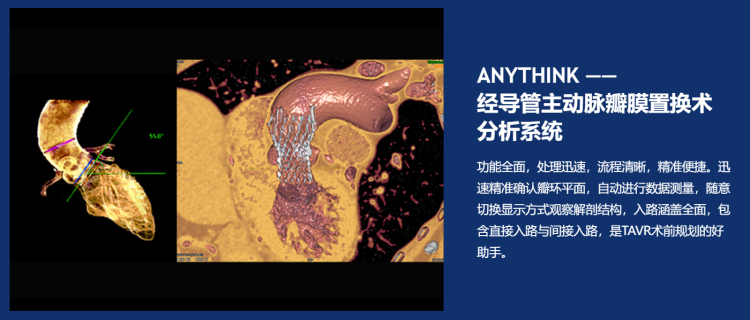

ANYTHINK 经导管主动脉瓣膜置换术分析系统